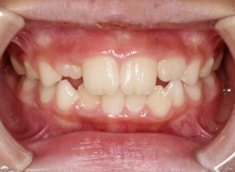

症例紹介

小児期ケース:叢生(ガタガタ)

治療法:拡大プレート+フルパッシブブラケット(クリアスナップ)

治療前